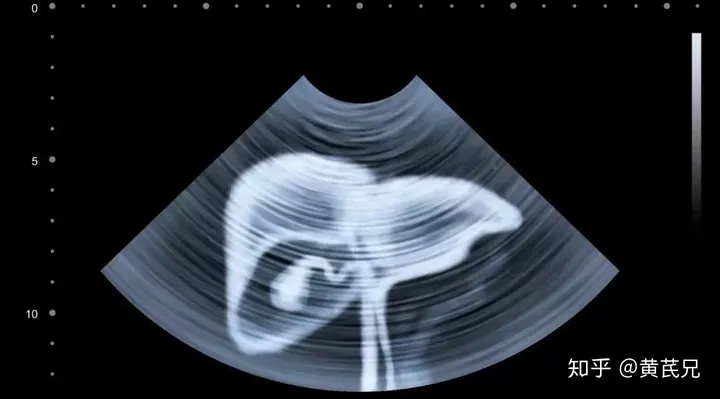

如果是前三类人(有乙肝、有肝硬化、家中有肝癌患者):建议每 6 个月做一次腹部 B 超检查 + 血清甲胎蛋白(AFP)检查;如果是后两类人(超过 40岁、爱喝酒):建议每年体检一次,发现异常再考虑上面的检查。当然,自己注意健康的同时,也要关注家人的身体状况。